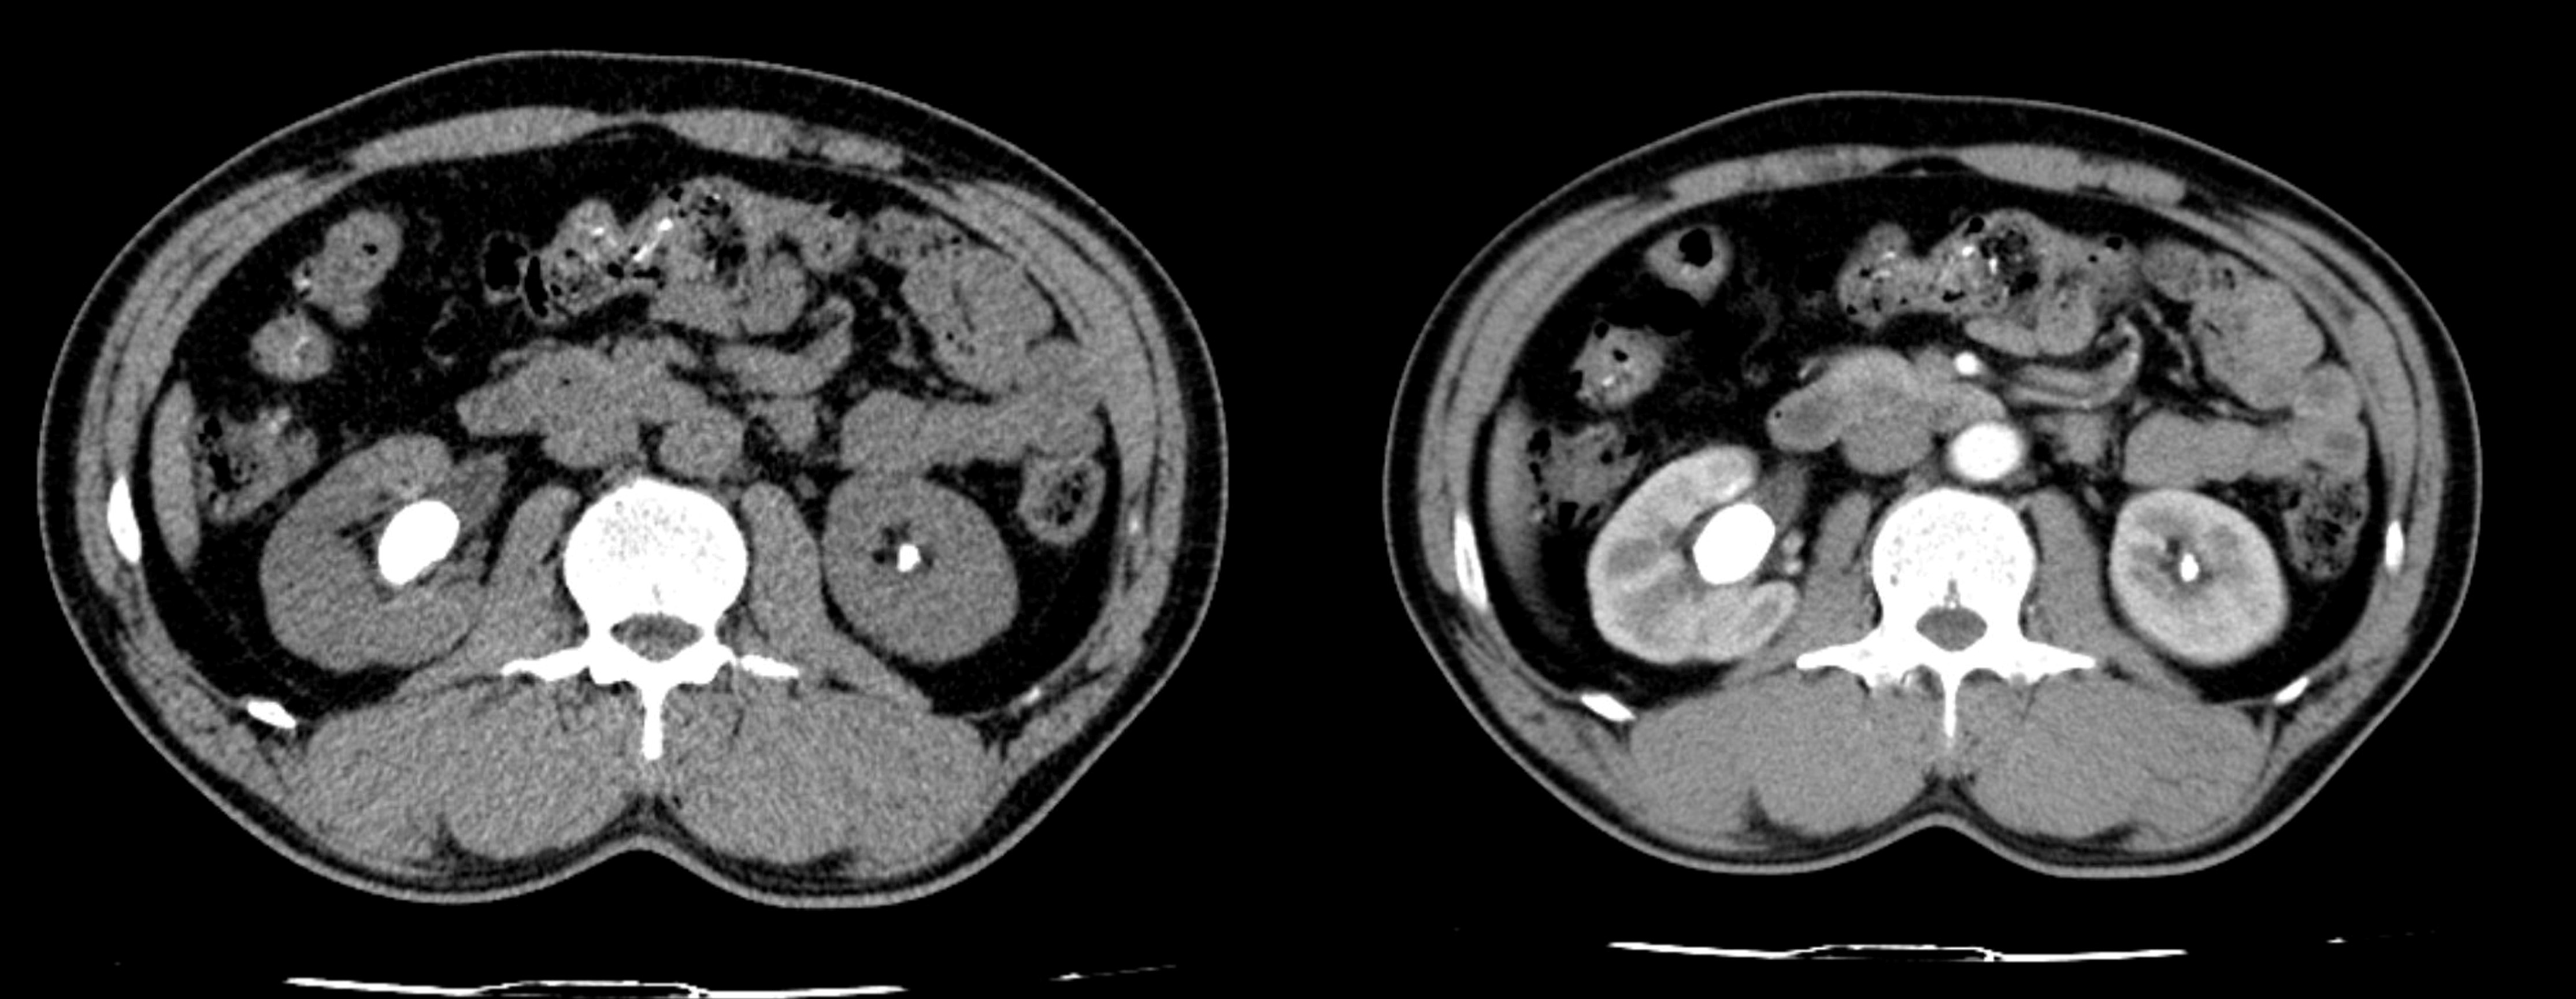

Hình 1: Phim CT scanner sỏi của bệnh nhân

Bệnh nhân nam 51 tuổi tiền sử mổ mở lấy sỏi thận P cách 15 năm vào viện do đau hông lưng bên P nhiều ngày tự điều trị thuốc nam không đỡ BN đi khám phát hiện sỏi thận P tái phát, BN nguyện vọng vào viện điều trị phẫu thuật. BN nhập viện được làm các xét nghiệm cơ bản, CĐHA chụp CLVT hệ tiết niệu có hình ảnh Ứ nước thận P, sỏi thận P 01 viên kích thước 18×22 mm , sỏi thận 01 viên kích thước 7x5mm.